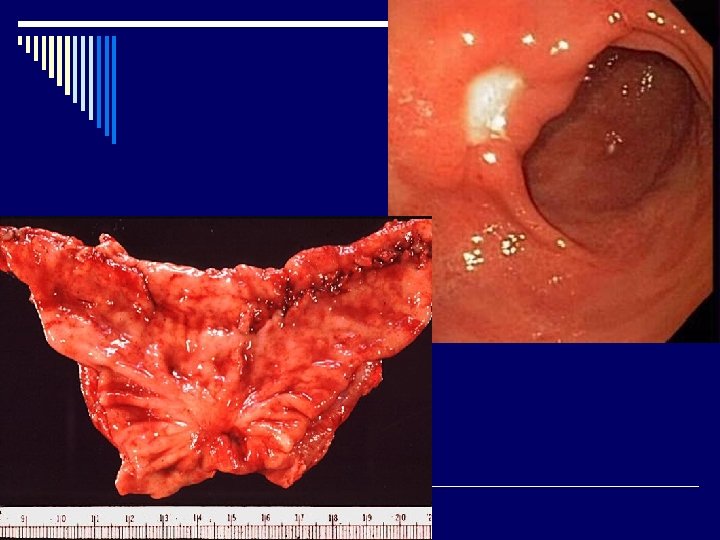

Диагностика 1. Эзофагогастродуоденоскопия с прицельной биопсией, цитологическим и гистологическим исследованием биоптата. - На основании эндоскопии выделяют морфологические изменения слизистой желудка: а)эритематозный (поверхностный); эрозивный, геморрагический гастрит; б)атрофический (умеренный, выраженный); в)гиперпластический - По изменениям эндоскопической картины выделяют три степени активности (I, III степени)

Язва желудка (язвенная болезнь желудка) (Шифр R 25) Язва двенадцатиперстной кишки (язвенная болезнь двенадцатиперстной кишки) (Шифр R 26) o Язвенная болезнь (ulcus gasteris et duodeni) (пептическая язва)– хроническое рецидивирующее заболевание организма, которое характеризуется формированием язвенного дефекта слизистой оболочки желудка или двенадцатиперстной кишки, склонное к прогрессированию, сопроваждается болевым, диспепсическим, интоксикационным синдромами, нарушением секреторной и моторной функции желудка.

При обострении язвенной болезни обнаруживается язва, хронический активный гастрит, чаще – активный гастродуоденит, ассоциированные с Нр. В структуре гастроэнтерологических заболеваний язвенная болезнь составляет от 1, 7 до 16, 0 %. Чаще всего болеют подростки в возрасте 15 -17 лет. Чаще встречается язва 12 -типерстной кишки (8287 %), реже слизистой желудка (11 -13 %).